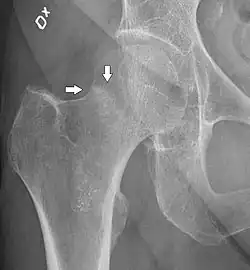

4) Данные рентгенологического обследования — выполняется рентгенография тазобедренного сустава в прямой проекции. Наличие линии перелома на рентгенограмме служит окончательным, объективным подтверждением предварительно выставленного диагноза. Иногда для постановки диагноза может потребоваться магнитно-резонансная томография или компьютерная томография.

В большинстве случаев достаточно выполнения рентгенограммы в прямой проекции. В ситуациях, когда есть подозрение на перелом шейки бедра, но оно не выявлено на рентгеновском снимке, следующим методом исследования является КТ. В редких случаях для подтверждения диагноза используется МРТ - диагностика.

Случай, демонстрирующий возможный порядок исследования изначально незаметных проявлений: